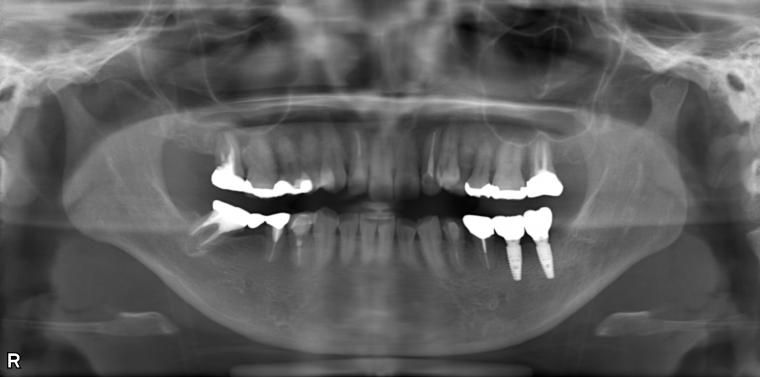

AFTER

第一大臼歯と第二大臼歯をインプラント、第二小臼歯をクラウンでの治療を希望されました。

現在も定期健診で拝見させていただいています。